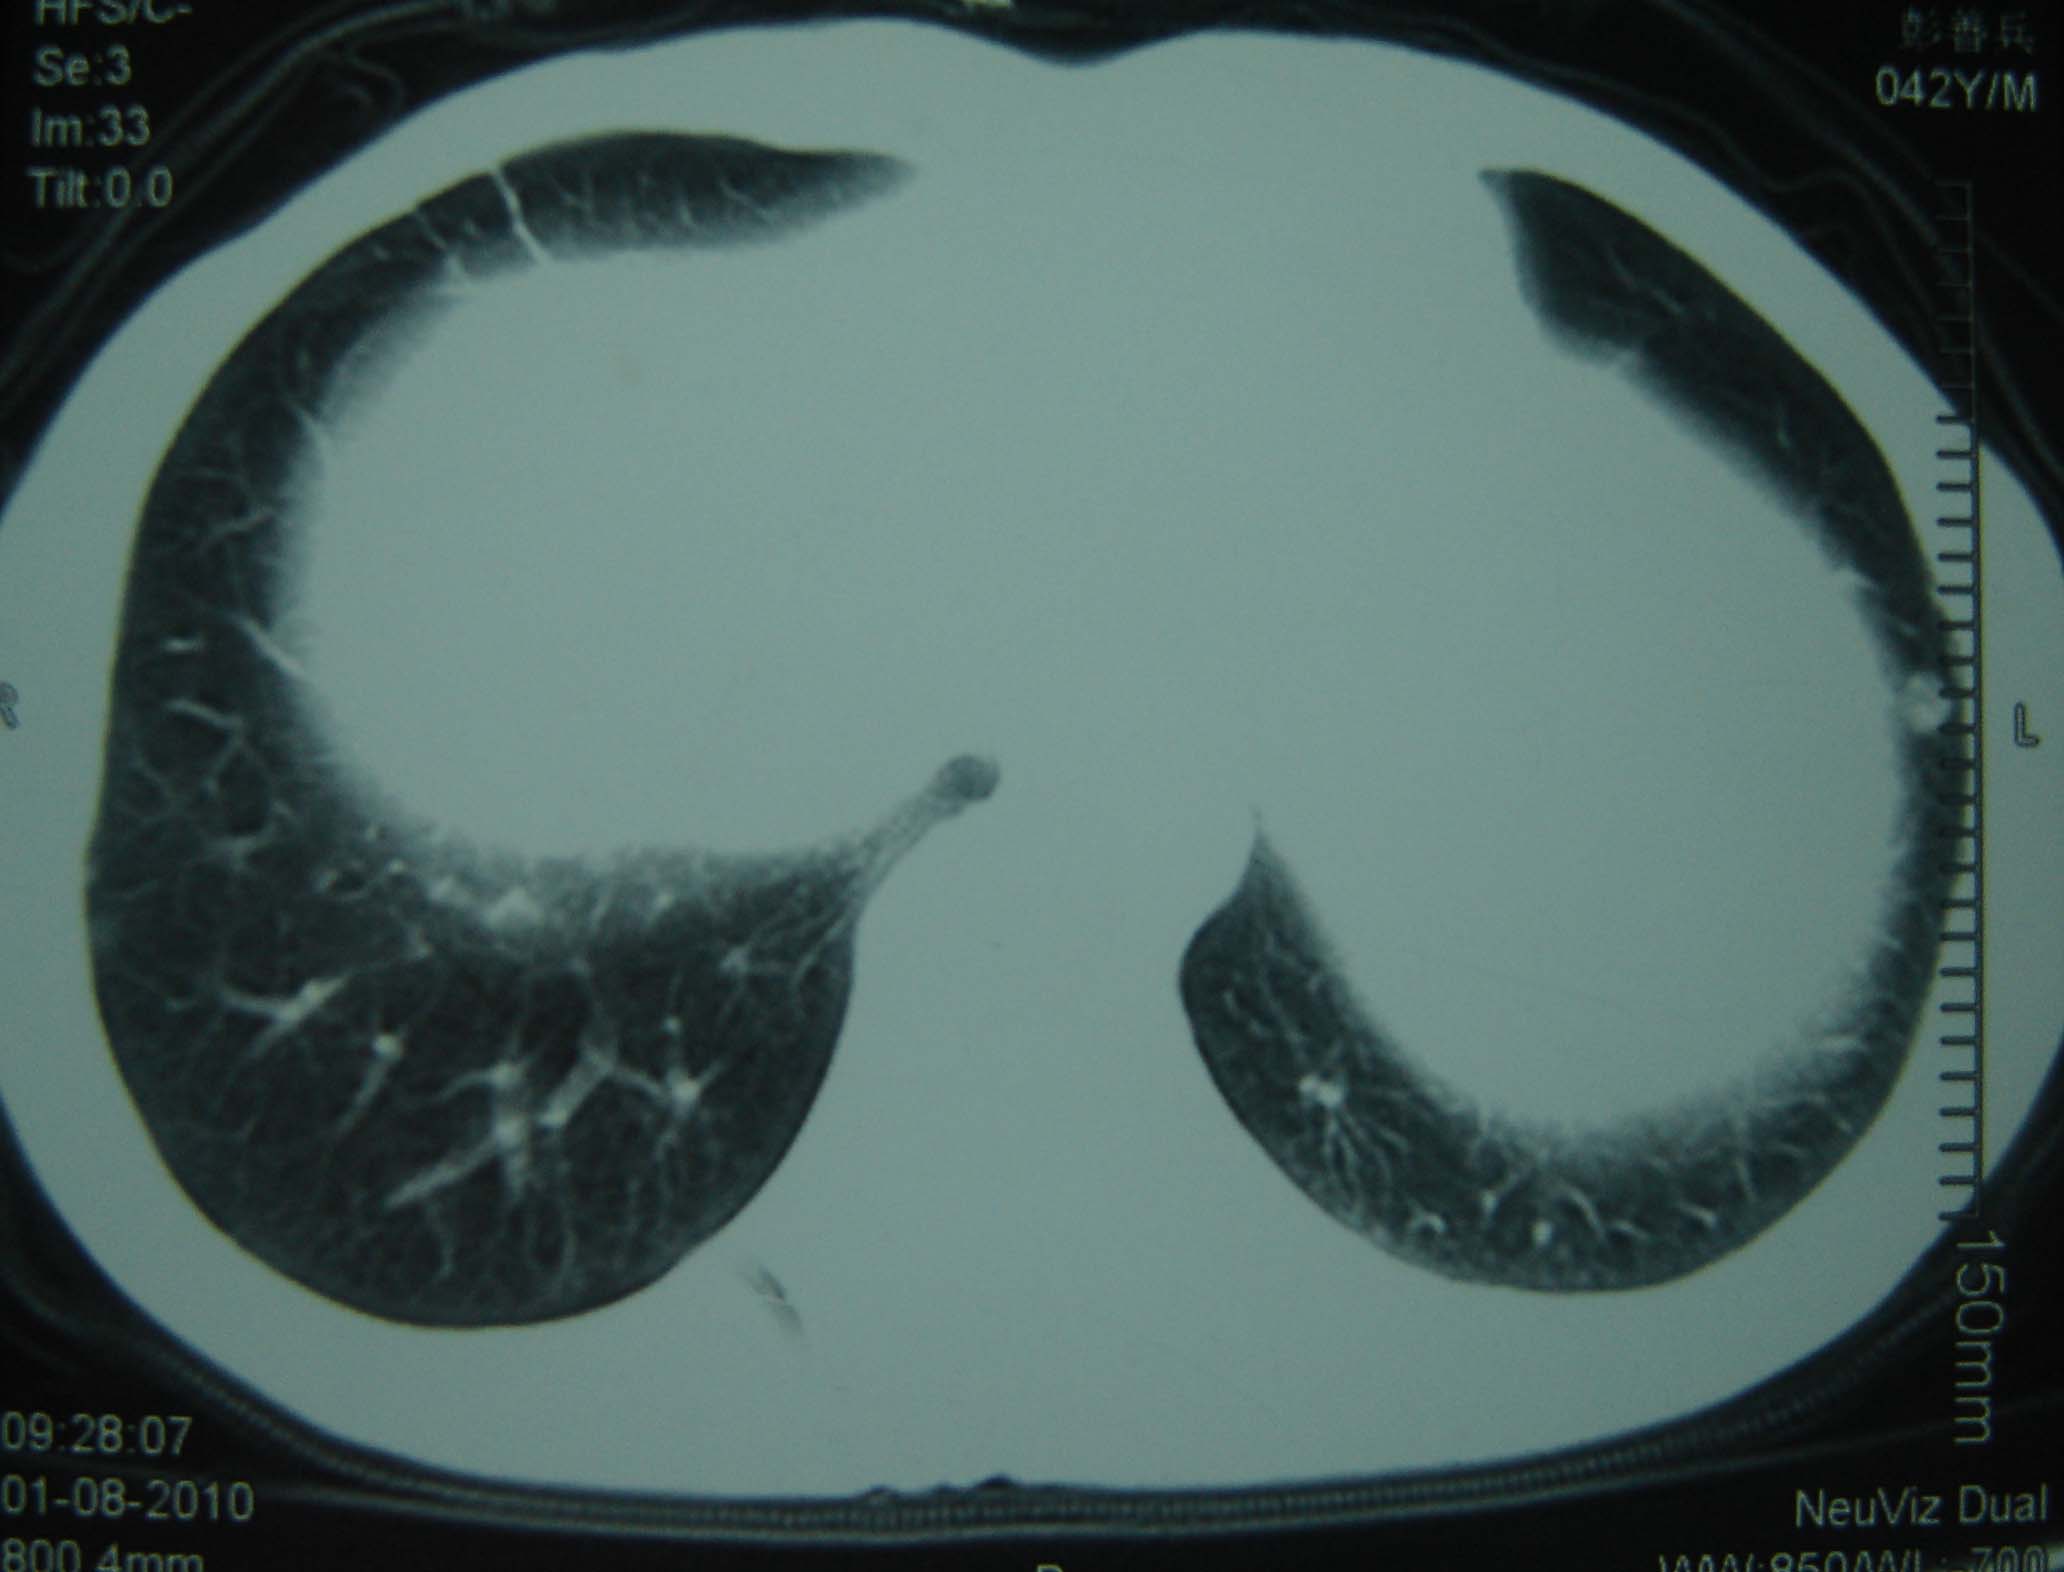

标题: CT25321:两肺多发结节 请会诊 [打印本页]

标题: CT25321:两肺多发结节 请会诊

男 、43岁,咳嗽胸痛,装修工,平时接触粉尘较多,有吸烟史10多年,纤维支气管镜检查未发现异常,胃镜、腹部b超检查亦未发现异常,颈部淋巴结活检未发现肿瘤细胞。

不能排除转移,如果不能找到原发灶,只有短期随访。

结节病?转移瘤?

1)考虑双肺及胸膜多发性转移瘤。2)肺气肿。